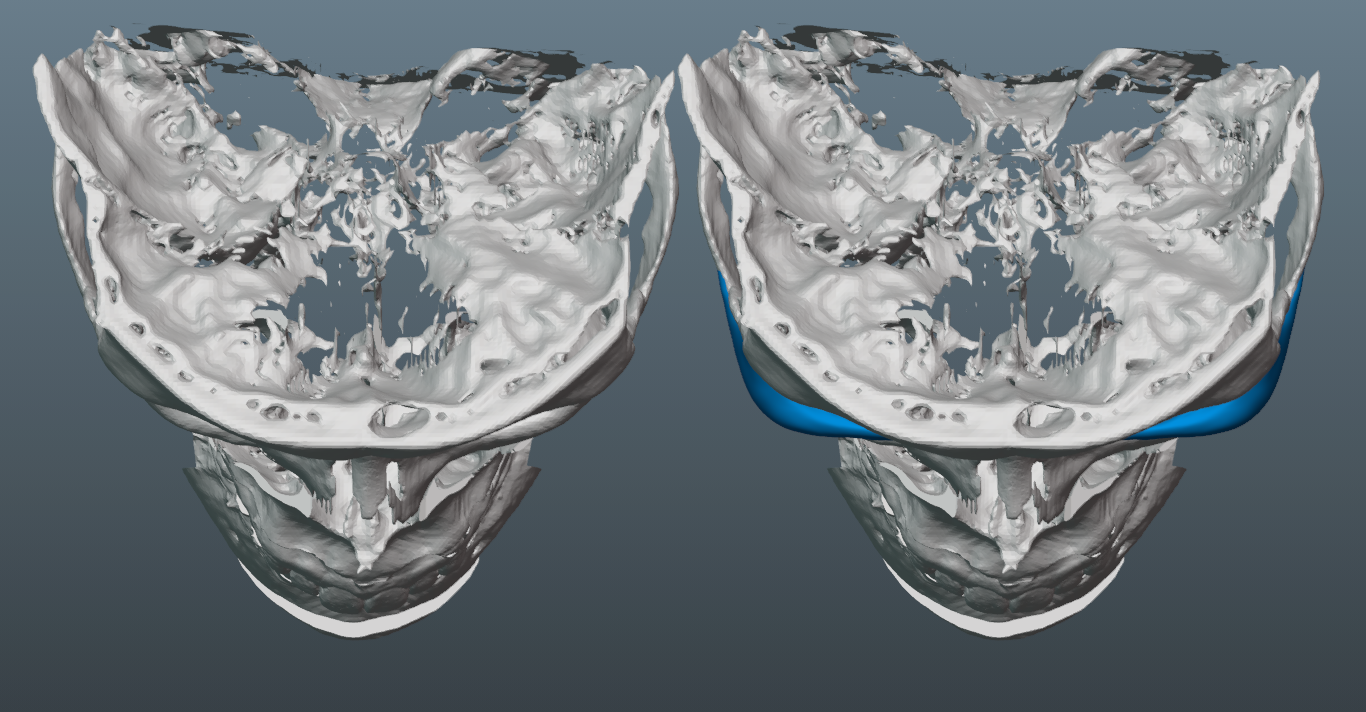

Trimax with around 7mm forward movement and 4mm downgraft.

Needed a lot of projection on the malar part of the implant, since the patient has a fairly flat midface, which would have been exacerbated by the bimax.

-Though we initially tried to do a smaller implant, it became clear that it was necessary to increase its size, so that we could ensure better transitions to the submalar region, zygo arch and lateral orbital rim.